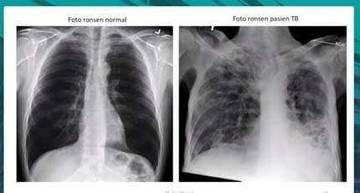

Hingga 2026 Puskot Atambua Catat 63 Kasus TBC

Stigma Klenik Masih Hambat Pengobatan TBC di Belu